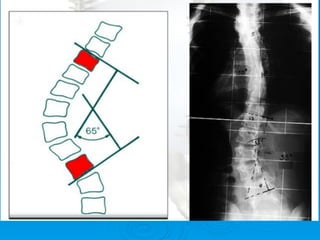

Método de Cobb: para medición del

grado de curva de la escoliosis

Ø    Se traza una línea paralela a la

superficie de los cuerpos de los

extremos de las curvas y luego

una línea perpendicular a la

línea ya trazada: el ángulo que

se forma con estas dos líneas

perpendiculares es el ángulo

que representa la magnitud en

grados de la desviación de la

columna. Las vértebras de los

extremos de la curva son los

últimos que miran hacia la

concavidad de ella.

Método de Cobbs

Método de Cobb:para medición del grado de curva de la escoliosis Ø  Se traza una línea paralela a la superficie de los cuerpos de los extremos de las curvas y luego una línea perpendicular a la línea ya trazada: el ángulo que se forma con estas dos líneas perpendiculares es el ángulo que representa la magnitud en grados de la desviación de la columna. Las vértebras de los extremos de la curva son los últimos que miran hacia la concavidad de ella.

• 130.